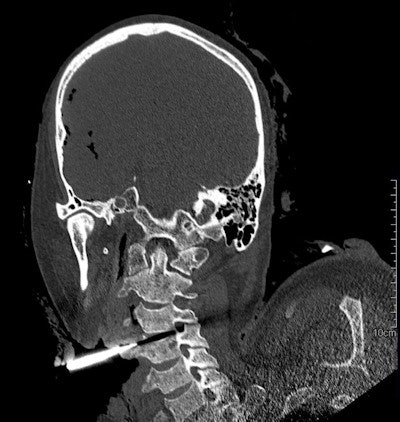

3D-rendered image shows the exit wound of a ballistic projectile in a neutral bloodless manner favored by juries and investigators. Image courtesy of Dr. Thomas Ruder.Ruder often uses a side-by-side comparison of antemortem images from local hospitals with postmortem CT images to identify subjects. Postmortem CT images may be reformatted to match almost any type of antemortem images, even high-quality ultrasound, he noted.